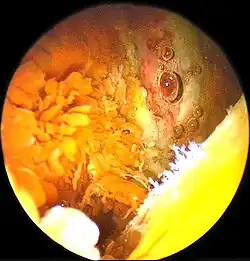

Nicht selten wird die PVS zufällig im Rahmen einer Gelenkspiegelung entdeckt. Es finden sich bei der diffusen Formen bräunlich-gelbe Schleimhautzotten. Bei der lokalisierten Erkrankung liegt ein umschriebener Tumor vor.